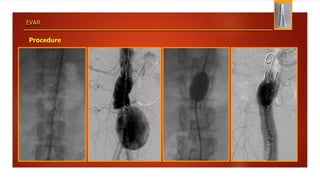

EVAR

Procedure